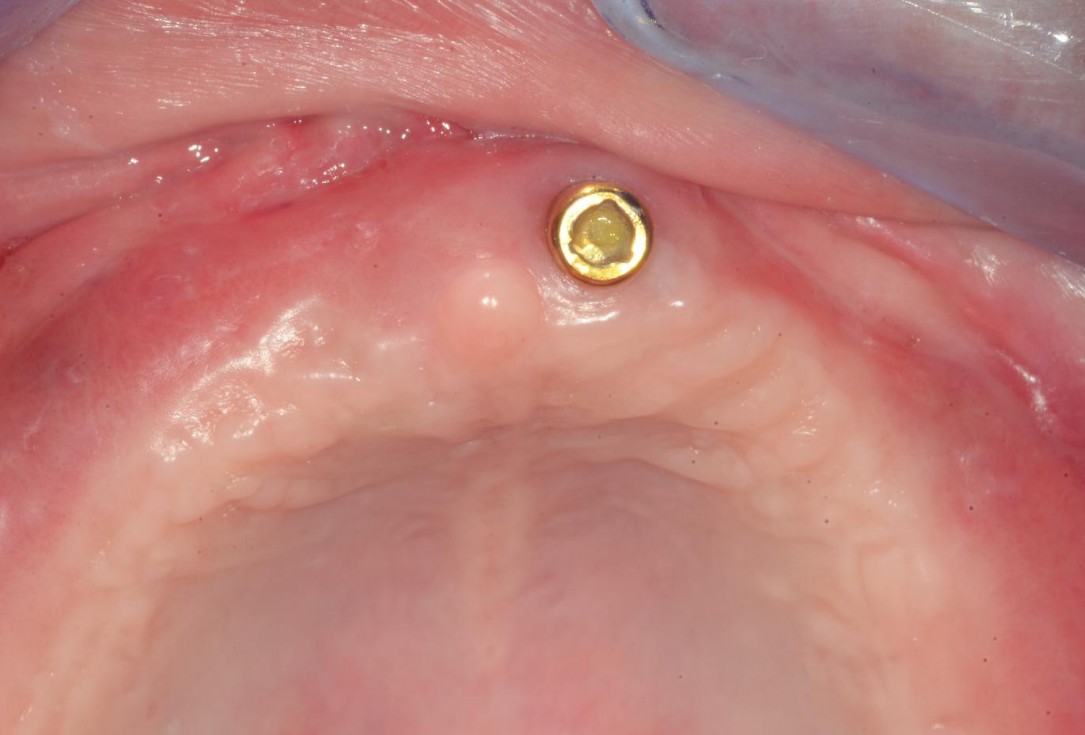

7/8 - Healing 4 weeks post-operativemucoderm® for full arch reconstruction of insufficient vestibular depth and lack of keratinized tissues - Dr. B. Mólnar & Prof. P. Windisch

8/8 - Post-operative healing at 6 months with excellent tissue maturation and favourable color and thicknessmucoderm® for full arch reconstruction of insufficient vestibular depth and lack of keratinized tissues - Dr. B. Mólnar & Prof. P. Windisch